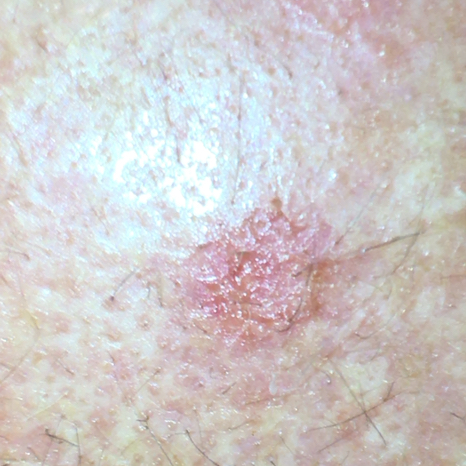

Aktinische Keratose führt häufig zu einer rötlich-braunen Hautfärbung mit erhabenen Stellen und einer rauen, krustigen Oberfläche. Denn die wörtliche Übersetzung von aktinischer Keratose bedeutet sonnenbedingte Verhornung der Haut. Die Kruste ist oft weiß, kann aber auch gelb oder braun sein. Die Flecken sind oft nur wenige Millimeter bis Zentimeter groß. Sie zeigen in der Regel keine Symptome, manchmal ein unangenehmes oder juckendes Gefühl. Diese Hautanomalie tritt häufig im Gesicht, an Handrücken, Armen, Beinen, Dekolleté, Ohrmuscheln oder bei kahl werdenden Männern an der Kopfhaut auf. In der Regel treten mehrere AKs auf der Haut auf.

Beispielfoto einer aktinischen Keratose